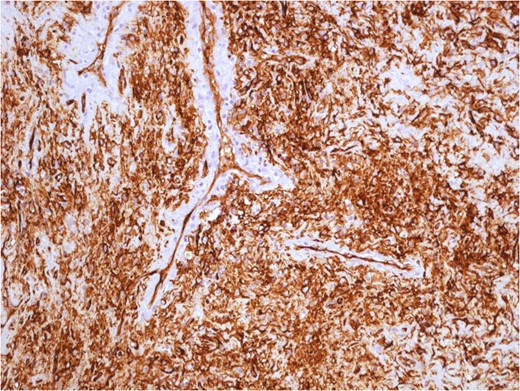

Variable cellularity and vascular patterns hemangiopericitoma-like in solitary fibrous tumour.

Uniform spindled cells in variably collagenous and vascular pattern. The tumour cells form random and trabecular arrangements.

The tumour cells have indistinct cytoplasm and oval nuclei, with inconspicuous nucleoli. Collagenous background is evident. Mitotic activity is absent. SPT cells are positive for BCL2 and CD34.

The histological appearance of SFTs may overlap with other benign and malignant diagnostic entities, such as hemangiopericytoma, leiomyoma, nodular fasciitis, inflammatory myofibroblastic tumour, fibromatosis and benign peripheral nerve sheet tumour [5]. In the past, SFTs were considered rare tumours originated from mesothelial cells. This has been recently proved using immunohistochemical analysis, particularly positive staining for CD34 and bcl-2 is an indication of SFT [5]. Usually, microscopic features are the presence of relatively spindled cell set in variably collagenous, cellular and in some cases myxoid matrix. An hemangiopericitoma-like vascular pattern in seen at least focally in most cases. Tumour cells have indistinct cytoplasm and oval nuclei, with inconspicuous nucleoli. Mitotic activity is low (<2–3 mitoses/10 HPF, high-power fields) in most cases, but some tumours show overtly sarcomatous features with a high mitotic activity.